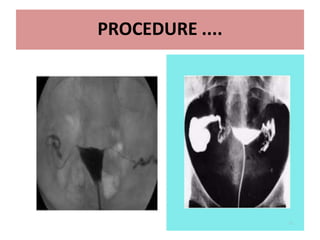

PROCEDURE ....

• Tenaculm is used to hold anterior lip of cervix .

• Speculum is removed & Patient is placed in slight

trendelenburg position and contrast is slowly given

• 3 ml contrast to fill uterine cavity and another 3 ml to

fill tube. ( up to 10 ml)

• 4 spot films are taken

• Additional oblique views may be taken for optimal

visualisation of pelvic pathology and tortuous fallopian

tubes( to see retroverted or anteverted)

• After end of the procedure , antibiotic course is given

and patient is informed about vaginal spotting for 1-2

days

13